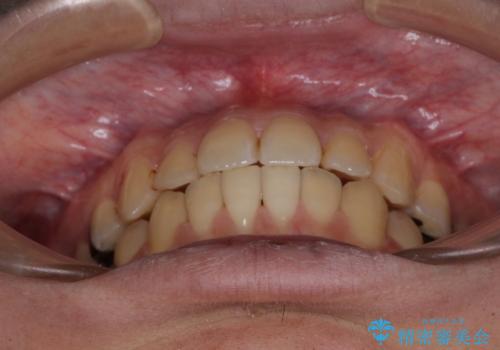

前歯のクロスバイトをインビザラインで矯正治療

- 前歯のデコボコとクロスバイトを気にして来院された患者様です。

前歯を早く整えたいとの希望があったので、ワイヤー矯正にて短期間でクロスバイトを解消し、その後インビザラインにて整えることとしました。